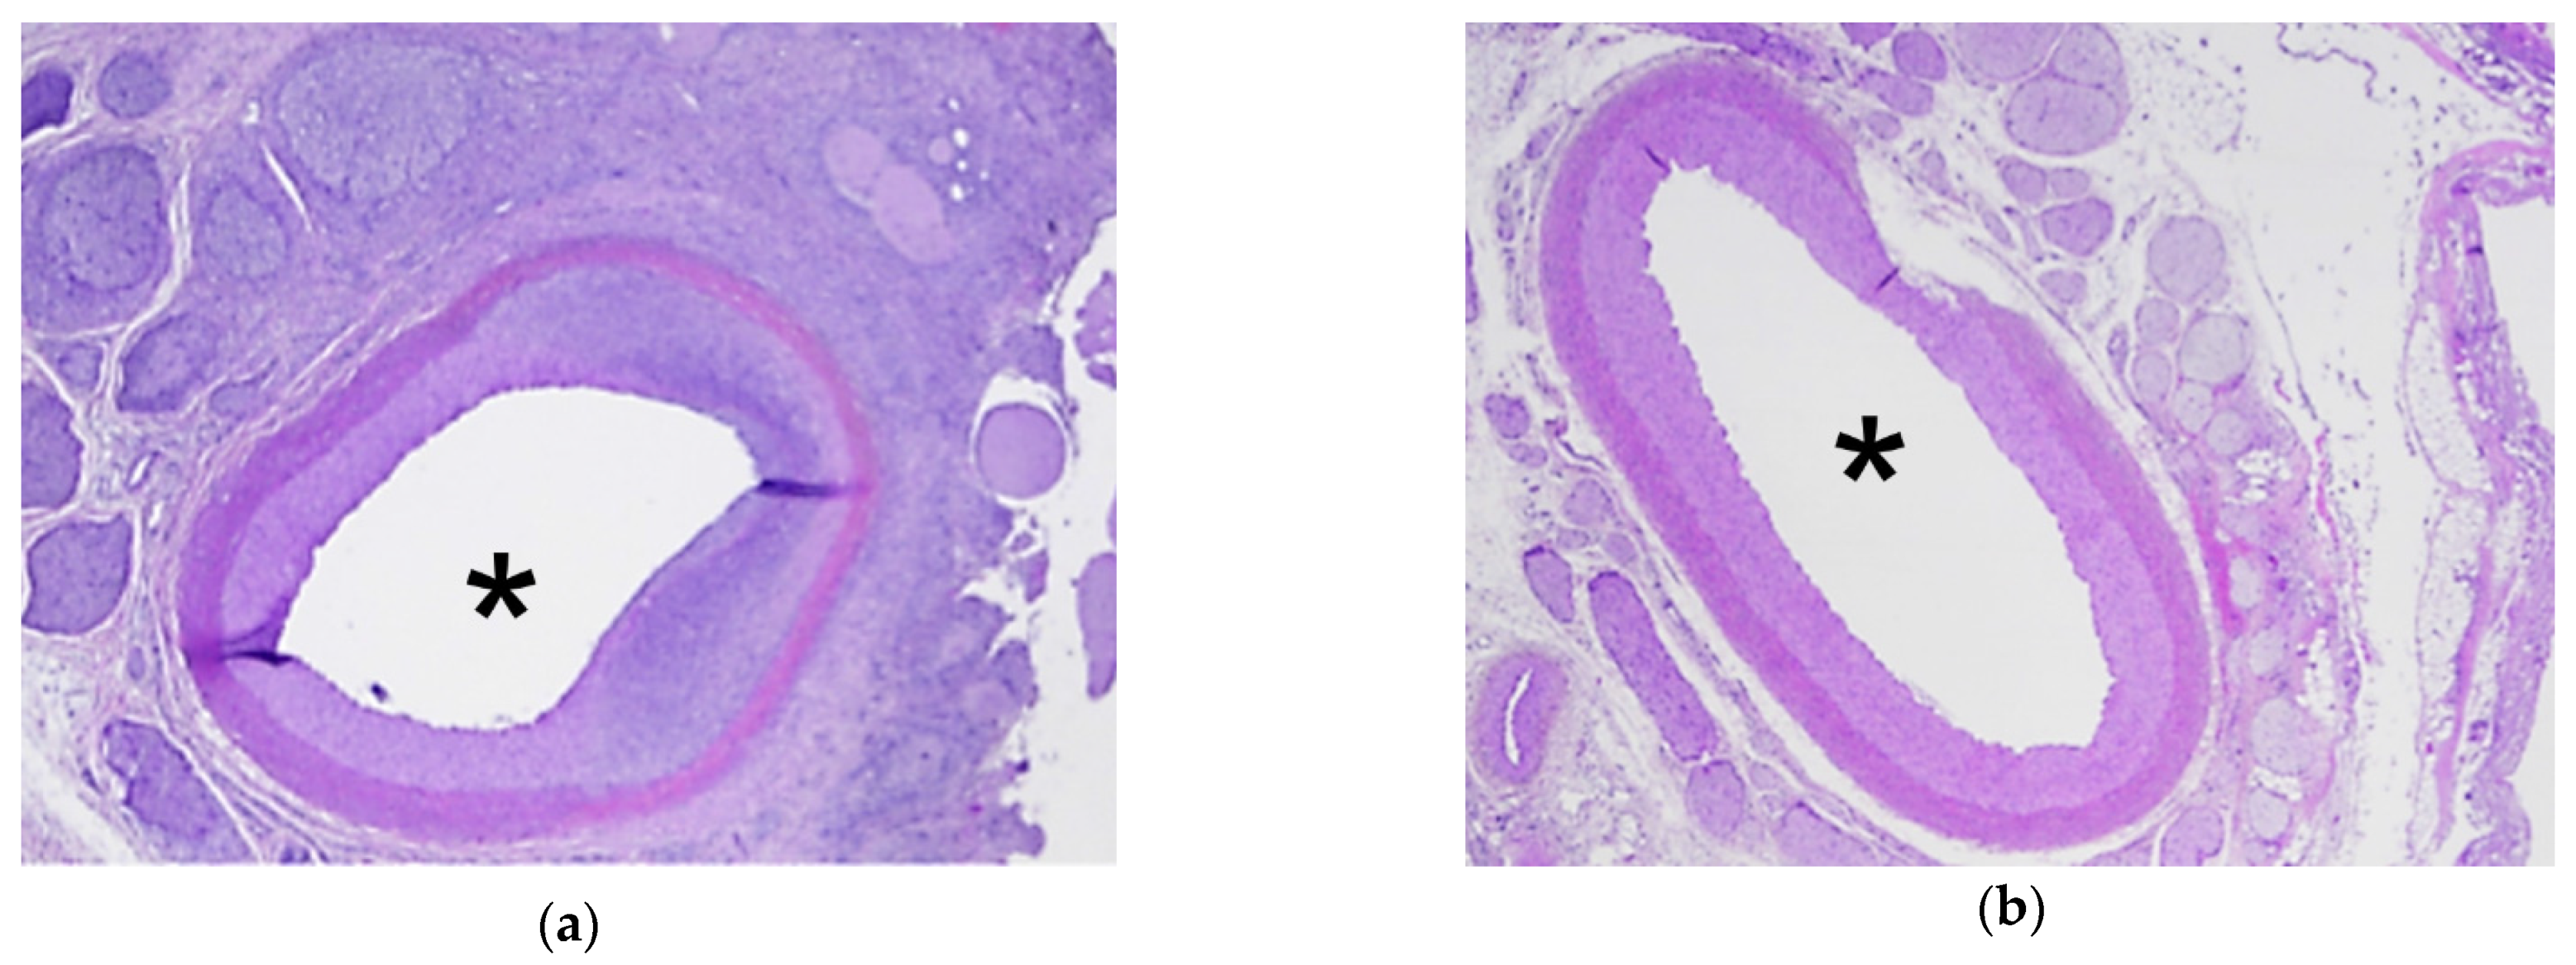

3.3. Analysis of HIFU Treatment